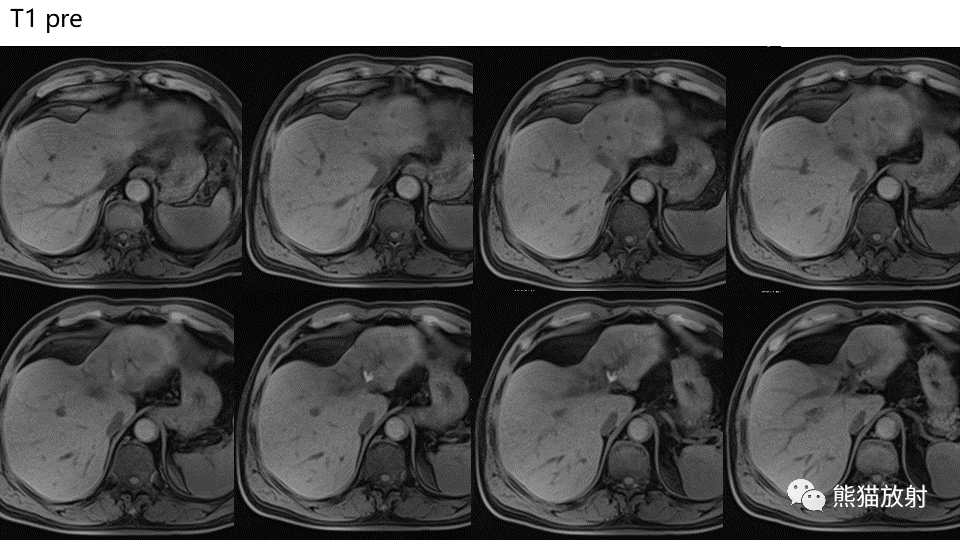

【PPT】肝内胆管细胞癌 VS 肝脓肿

【PPT】肝内胆管细胞癌 VS 肝脓肿-1